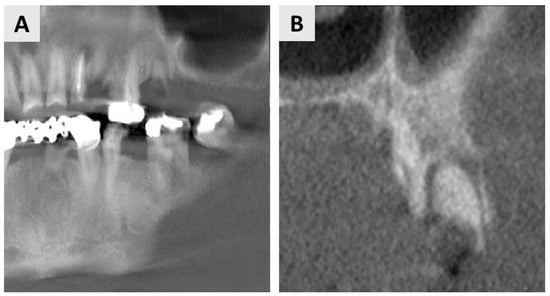

4. Case Report Two: GBR with Immediate Implant Placement